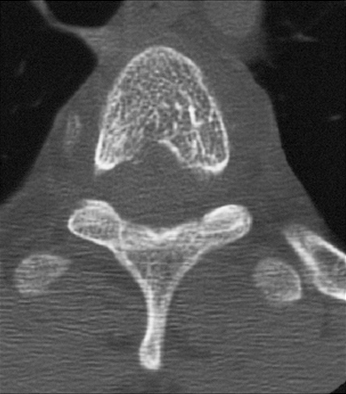

- Στην CT προεξάρχουν κάθετες γραμμώσεις αναμεσα σε περιοχές οστεοπενίας, ενώ μετά την χορήγηση ενδοφλεβίως σκιαγραφικού, η επισκληρίδια και παρασπονδυλική επέκταση του όγκου προσλαμβάνουν έντονα.